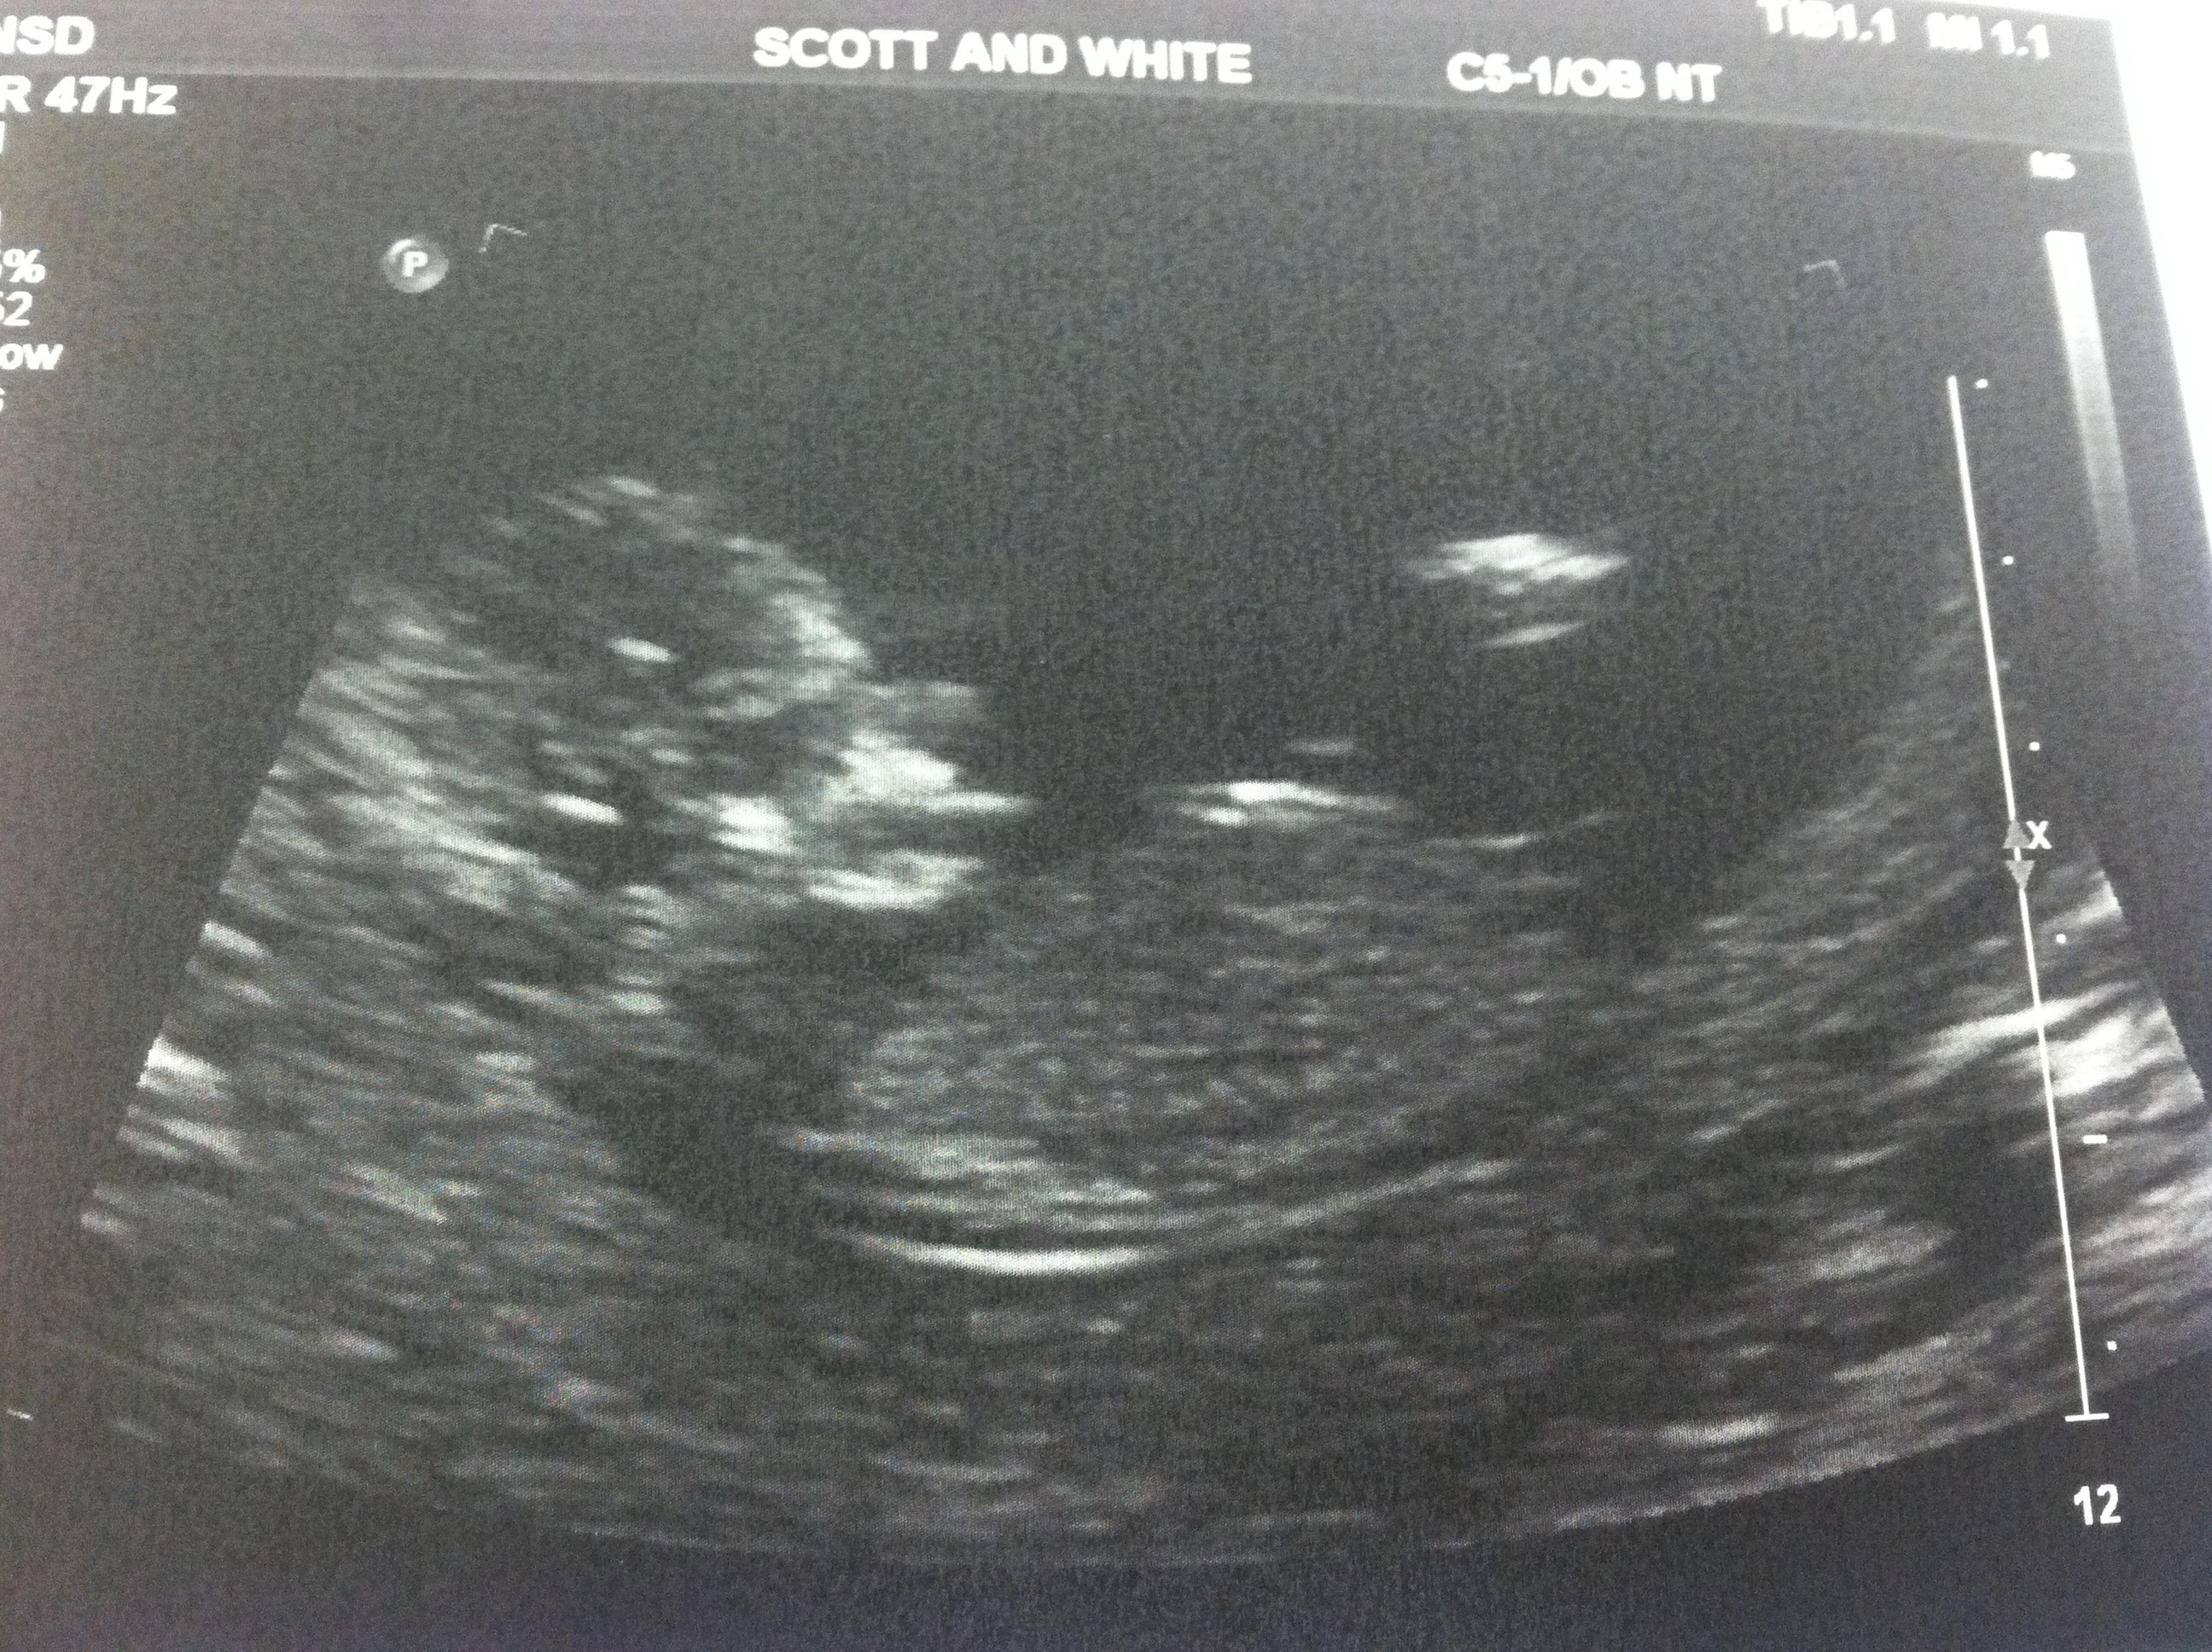

CONFIRMED TODAY AT 15 WEEKS- WE ARE EXPECTING A LITTLE GIRL! I think we are still in shock and the news hasn't really sunk in yet. My 5 year old is thrilled, but more surprising was my husband. He is probably the most excited of all. I did sway rather lightly, but I will make sure to post it in case it might help others. Thanks again for all of your guesses!

13w2d pics- ITS A GIRL!!! THANKS FOR GUESSING :)

You ladies just made my night! The tech made it clear that it was too early to make a gender prediction so I didn't ask, but I saw a long flat nub with a fork I THOUGHT. I convinced myself it was too good to be true. We would be happy with another boy but this is likely my last shot at a girl so I have some hope!